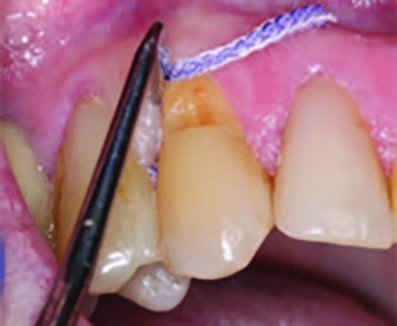

Figure 3. Application of caries indicator dye to identify the remaining infected tissue beneath the dislodged composite.